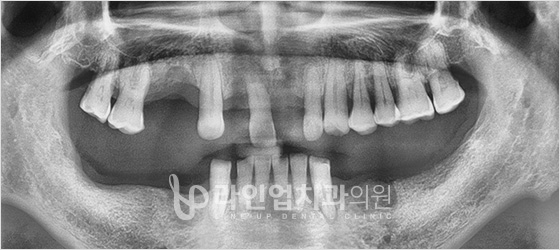

Before

After

Имплантация нижних моляров